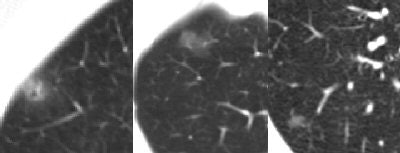

![]() |

| Nonsolid nodules have a higher probability of malignancy than solid nodules, but a lower probability of malignancy than part-solid nodules. |